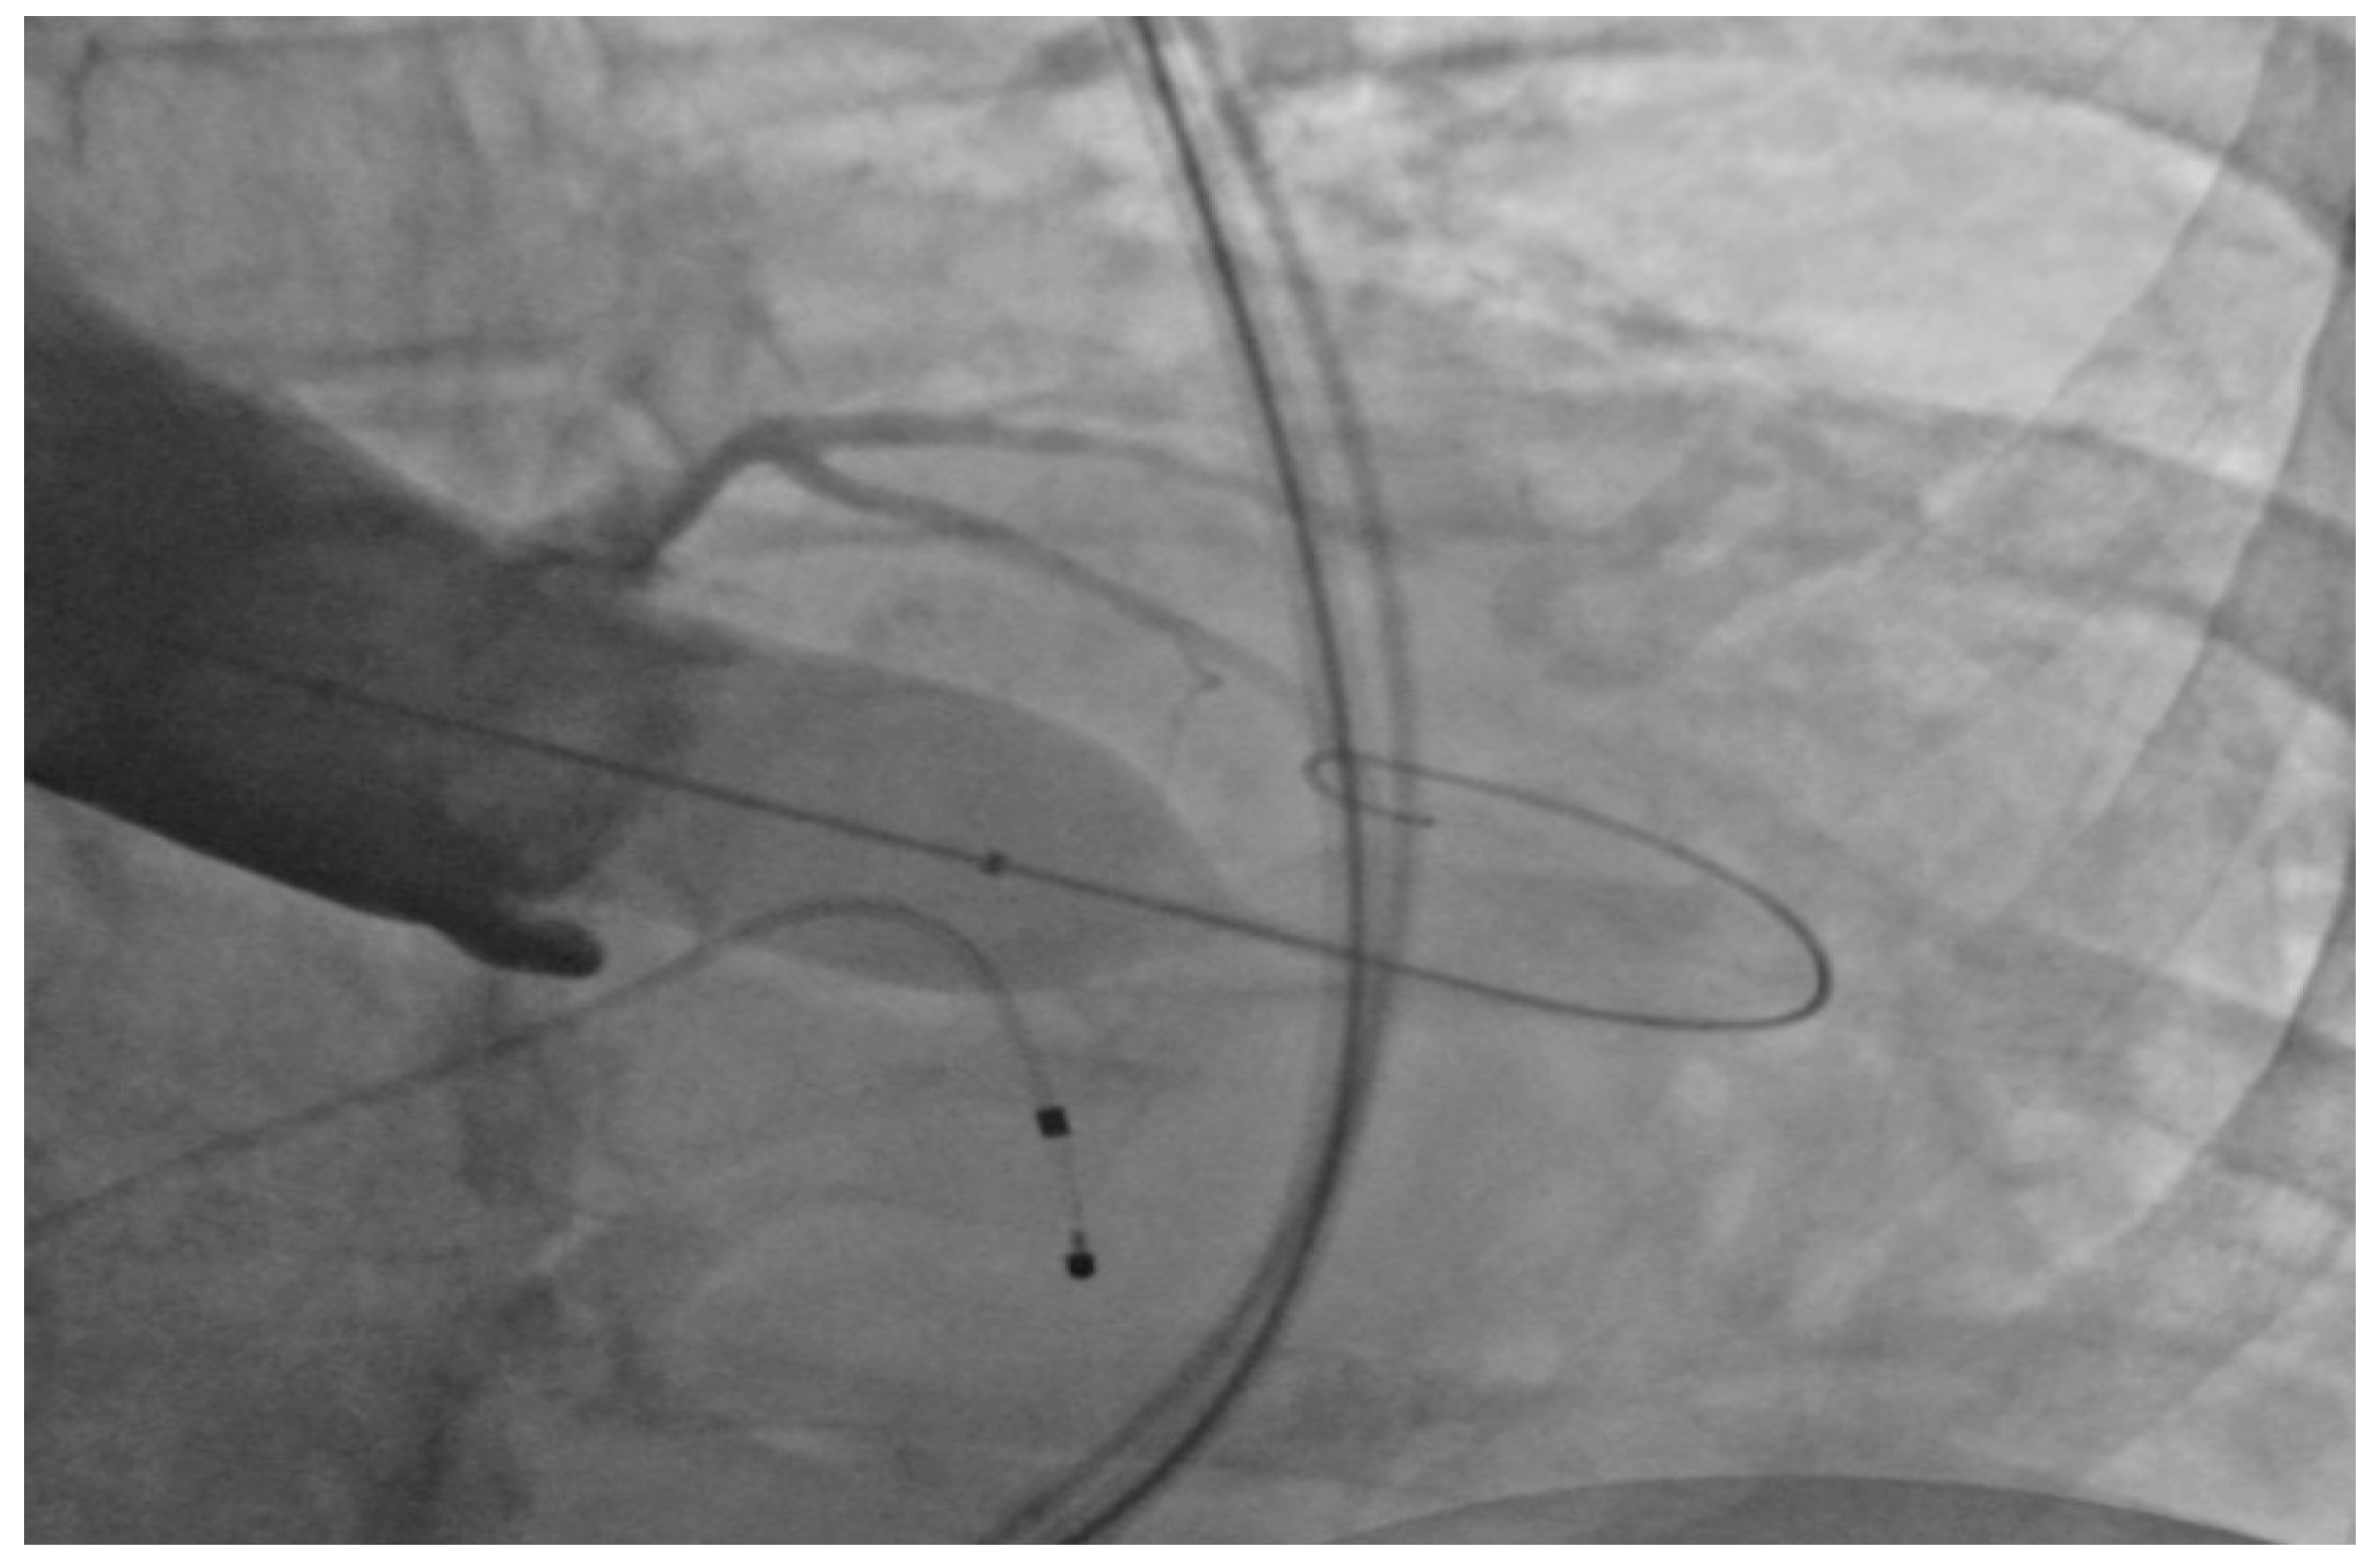

Under general anesthesia, the right and left femoral arteries were each accessed with 6-french sheaths. A temporary pacemaker was placed in the right ventricle through an 8-french sheath in the right femoral vein. Balloon valvuloplasty was performed by advancing a balloon via the right femoral artery sheath, and during rapid ventricular pacing at 160 beats per minute, inflating it across the aortic valve to clear the stenosis and to deploy the 26-mm SAPIEN S3 bioprosthetic aortic valve (Figure 1), which expanded within the native aortic valve (Figure 2). The purpose of rapid ventricular pacing during TAVI is to reduce cardiac output, which facilitates balloon inflation across the valve and placement of the bioprosthetic aortic valve. The mean valvular gradient after TAVI decreased to 1.9 mm Hg (normal is <5 mm Hg). There were no intraoperative complications. The patient was extubated and transferred to the coronary care unit with the temporary transvenous pacemaker, which was removed two days later.

Figure 2.

Expanded SAPIEN S3 valve within the native aortic valve.